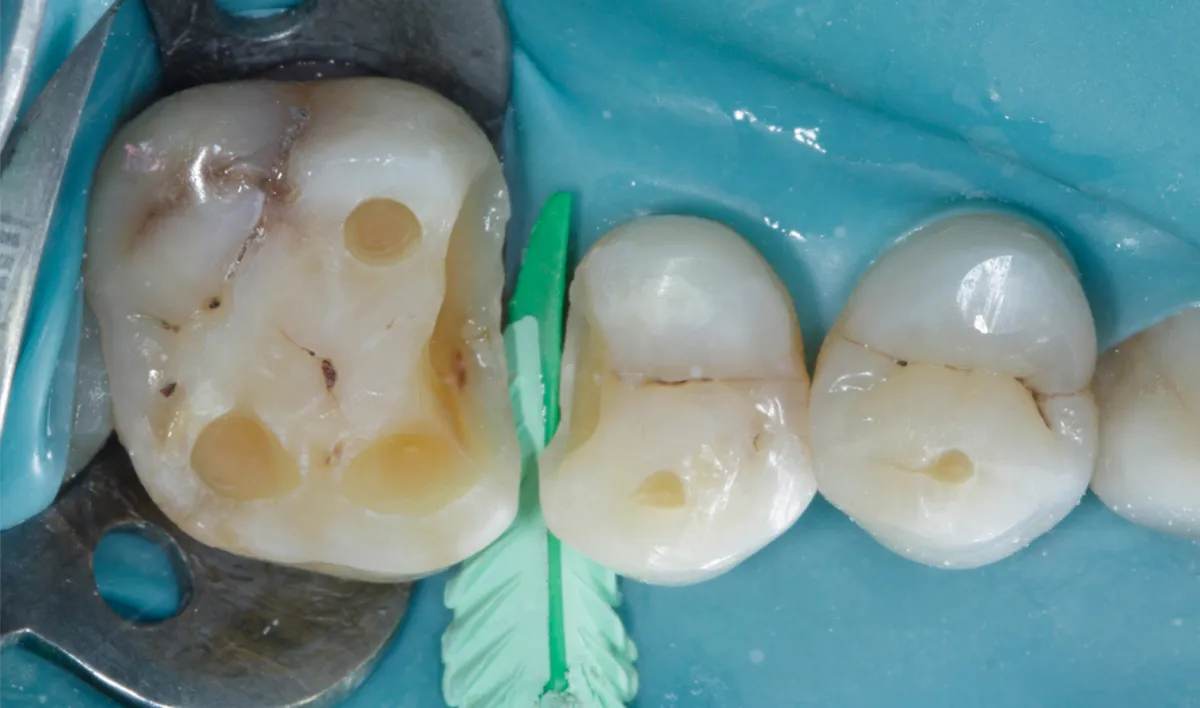

Selecting the appropriate sectional matrix system is crucial in such adjacent large defect cases so we choose Garrison Quad system. It is essential to ensure that the marginal ridge is correctly dimensioned and aligns with the occlusal anatomy. This alignment is vital for creating well-defined adjacent triangular fossae and a properly shaped occlusal embrasure. Therefore, the height of the marginal ridge largely depends on the choice of band height. Here we choose Firm band FXH 200

The firmness of the band material facilitates easy placement and secure fitting, they bands maintain their shape and do not distort during the composite injection molding procedure, ensuring accurate and reliable restoration outcomes.

The first band (FXH 200) was placed in the distal defect of tooth #15 and secured using a Large Quad Wedge (Figure 05).

Next, an identical band was inserted into the mesial defect of tooth #16 by slightly repositioning the wedge, allowing the band to pass beneath it. The wedge was then reinserted to its full length, holding the bands in place with gentle finger pressure, ensuring both bands were securely positioned beneath the wedge. (Figure 05)

Figure 05: The FXH 200 band was securely positioned using a Large Quad Wedge placed from Buccal, ensuring a tight seal.